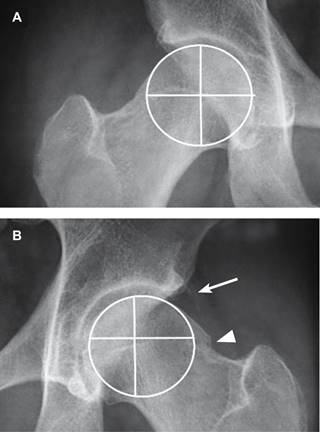

Figura 2: Acercamiento de la imagen anterior que muestra en (A) cadera derecha con eje normal de la cabeza femoral. B) Cadera izquierda con eje de rotación en un punto excéntrico a su centro geométrico que corresponde al diagnóstico de pinzamiento femoroacetabular en leva.